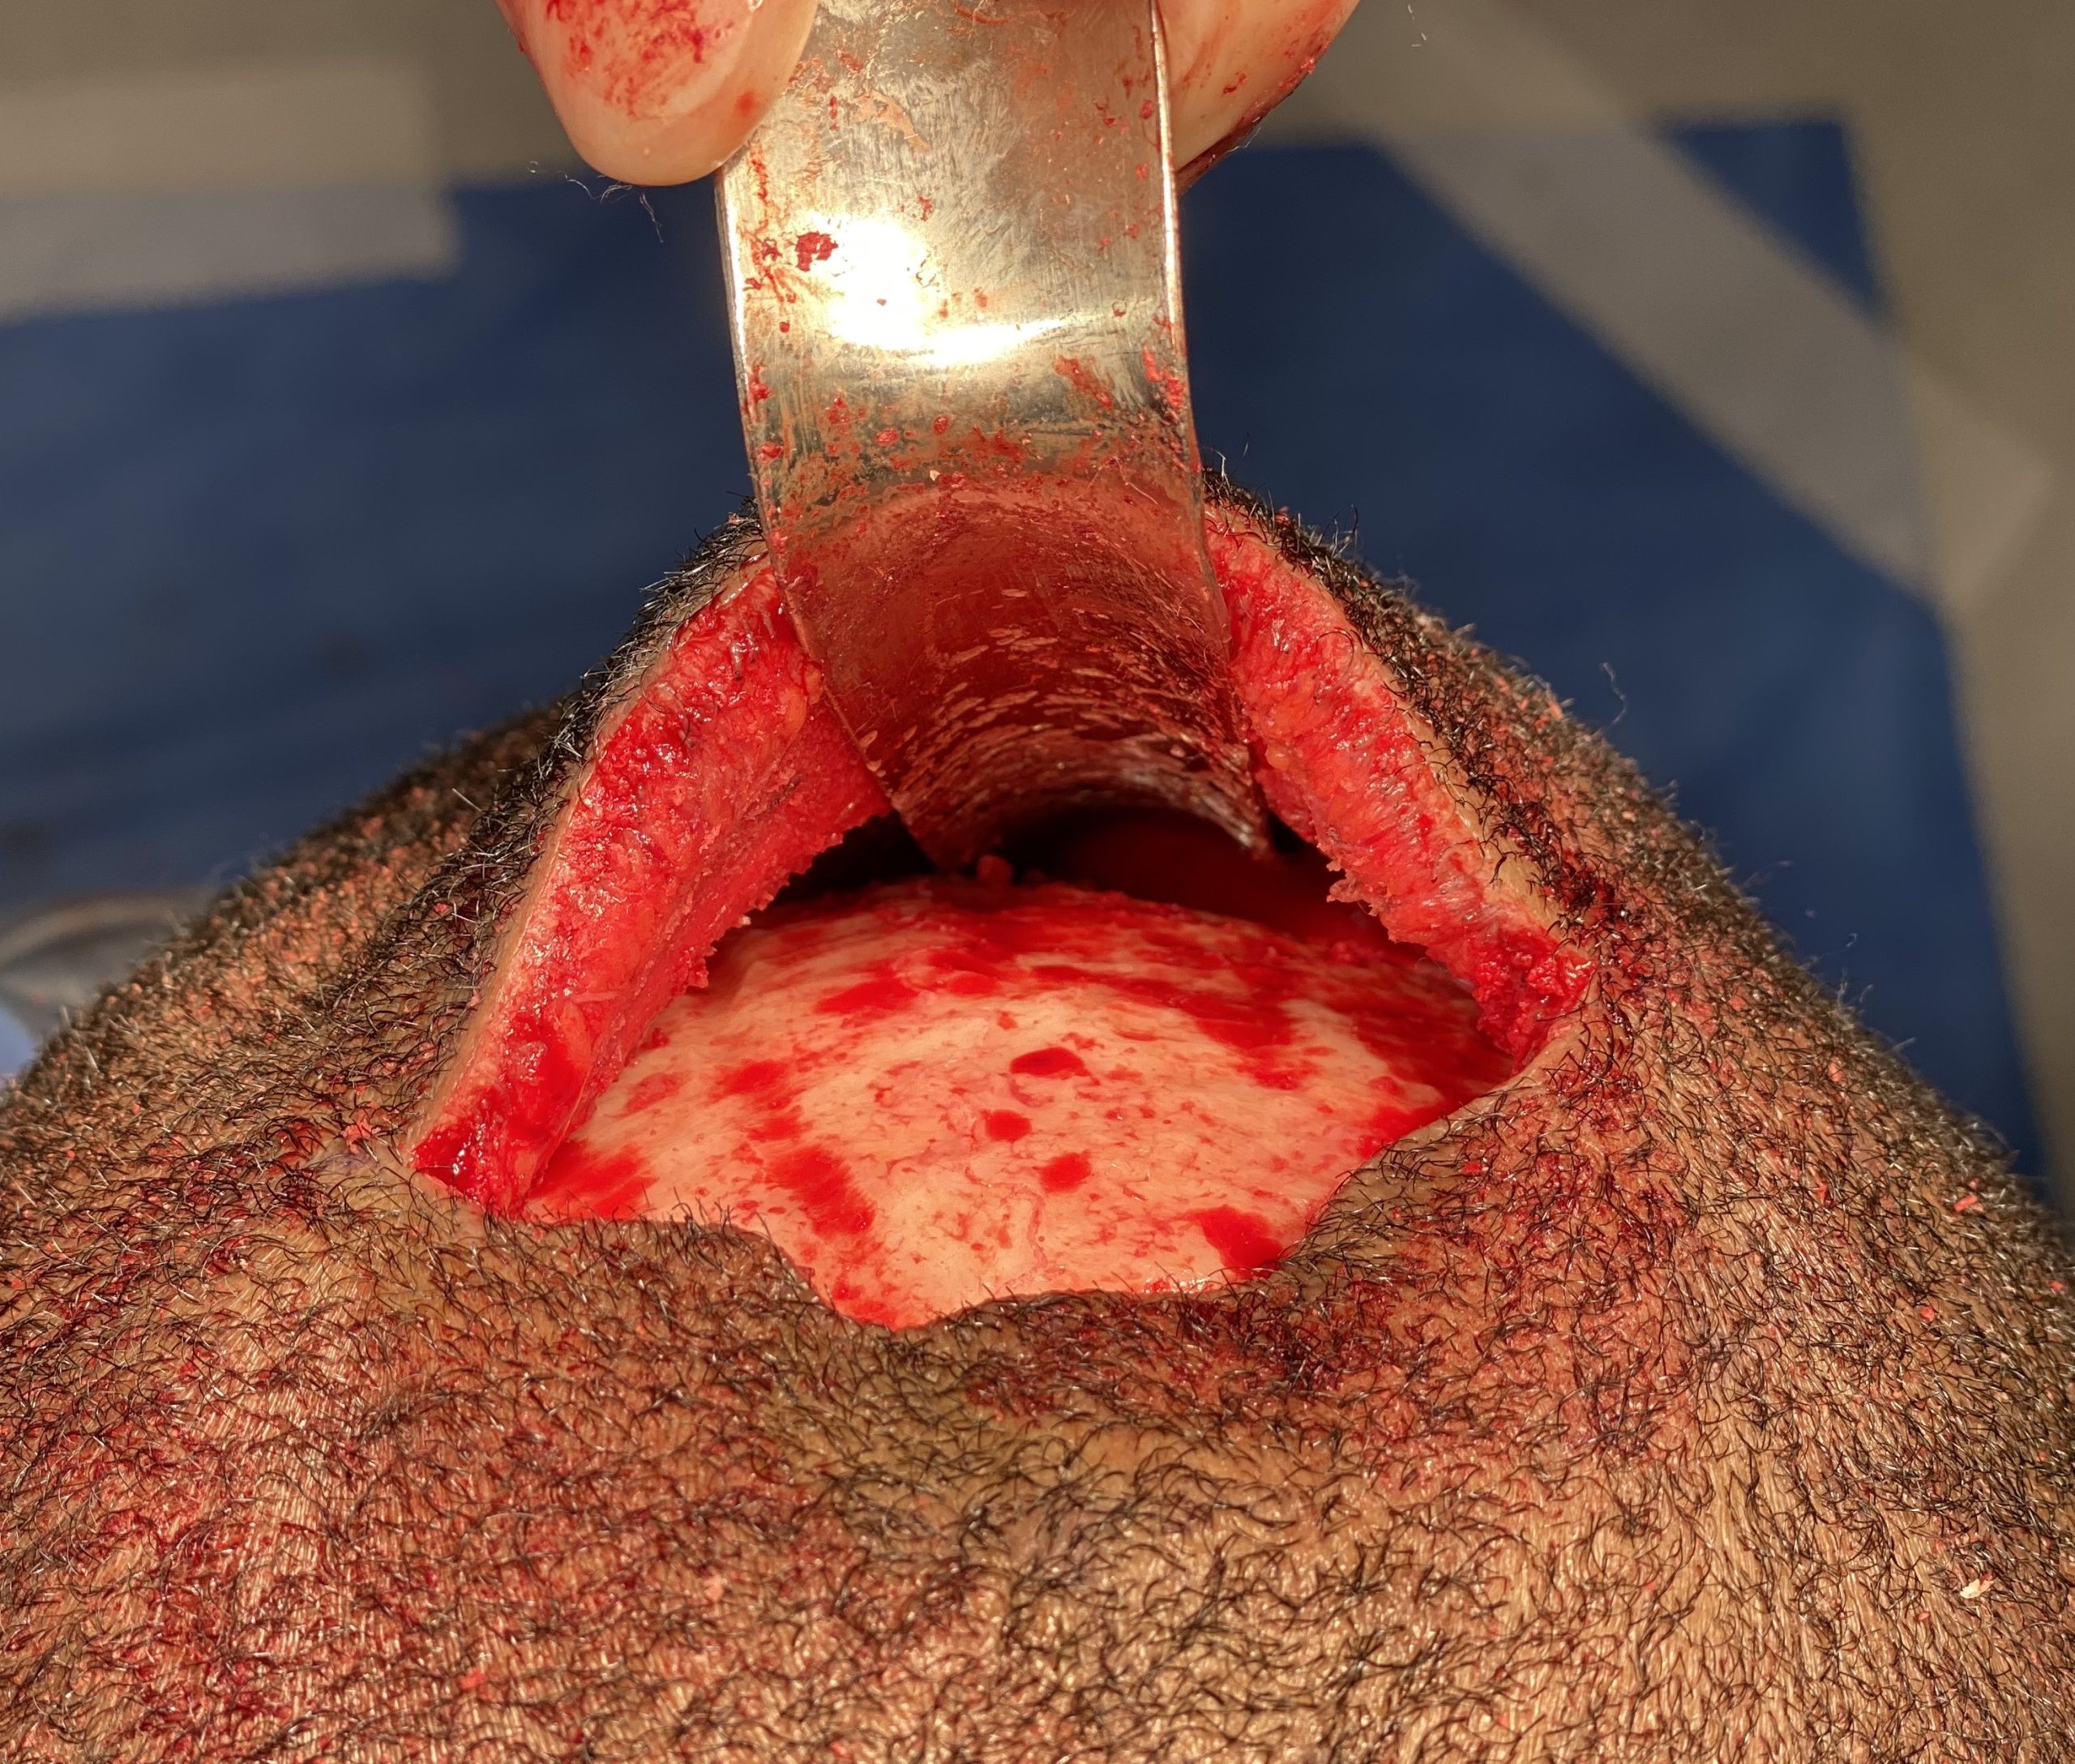

Desire for reduction of prominent occipital knob deformity.

Intraoperative result from occipital knob skull reduction through a direct small scalp incision.

Desire for reduction of prominent occipital knob deformity.

Intraoperative result from occipital knob skull reduction through a direct small scalp incision.